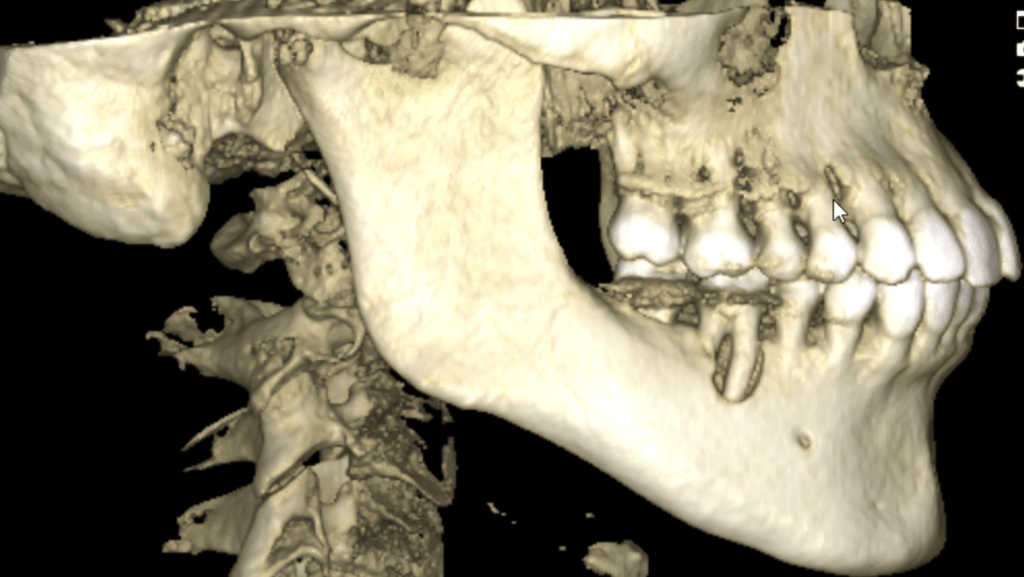

Vertical root fracture